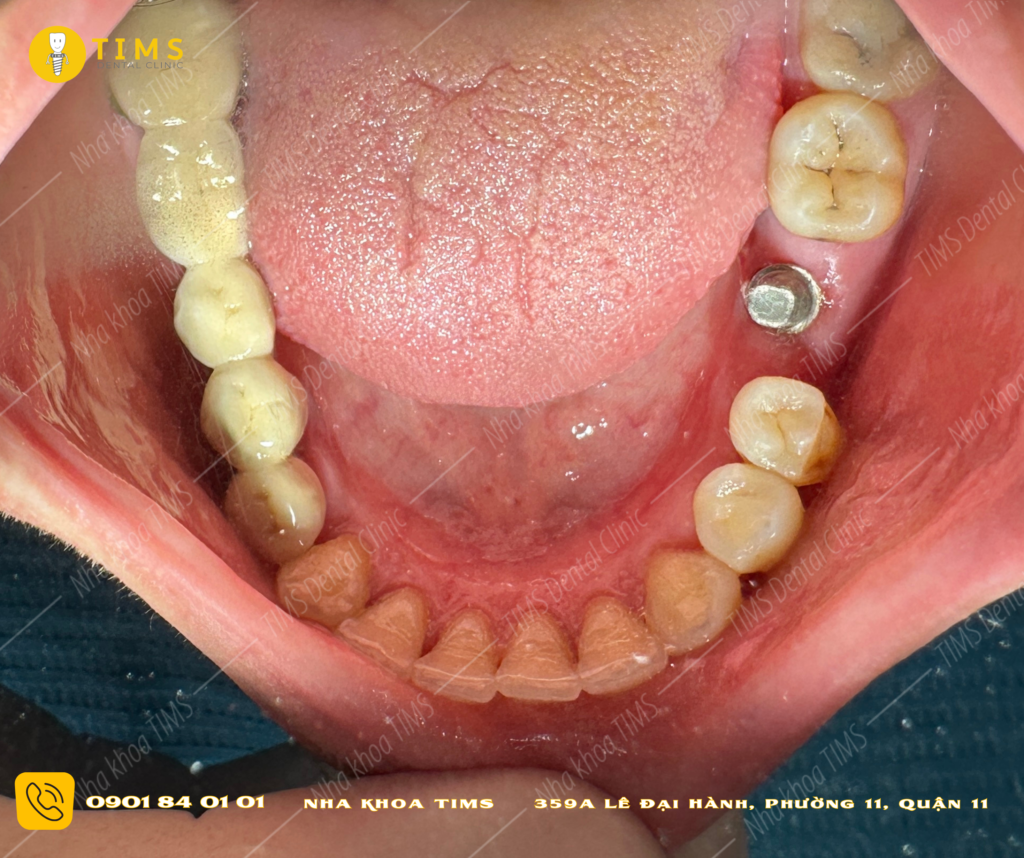

3. KHÔNG CẦN NHIỀU PHẪU THUẬT: Thông thường sau khi gắn implant thì Khách hàng phải chờ đợi vài tháng để đợi trụ tích hợp xương, sau đó chúng ta cần thêm 1 phẫu thuật để gắn ốc lành thương (healing). Nhưng với quy trình trồng răng implant 24 giờ thì Bác sĩ sẽ gắn răng giả ngay sau khi gắn implant nên chỉ cần 1 lần phẫu thuật duy nhất.

5. TÍNH THẨM MỸ: Răng giả được gắn ngay sau khi trồng implant sẽ được thiết kế phù hợp với hình dạng và màu sắc của răng gốc và khách hàng sẽ không lo ngại vì việc trống răng. Điều này mang lại kết quả thẩm mỹ ngay từ đầu.